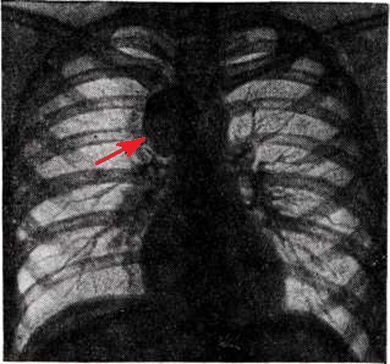

Рентгенологическая картина Ганглионеврома зависит от её локализации. Наиболее часто объектом рентгенологическое исследования является Ганглионеврома, растущая из элементов пограничного симпатического ствола и проникающая в паравертебральный отдел заднего средостения. На прямой рентгенограмме Ганглионеврома заднего средостения даёт однородное различных размеров затемнение полукруглой или полуовальной формы, тесно примыкающее к тени позвоночника. Очертания тени Ганглионеврома обычно чёткие и ровные (рисунок 2). В боковой проекции для Ганглионеврома характерна непосредственная близость к тени позвоночных концов рёбер. При затруднении определения локализации Ганглионеврома могут быть применены пневмомедиастинография (смотри) или искусственный пневмоторакс (смотри Пневмоторакс искусственный).